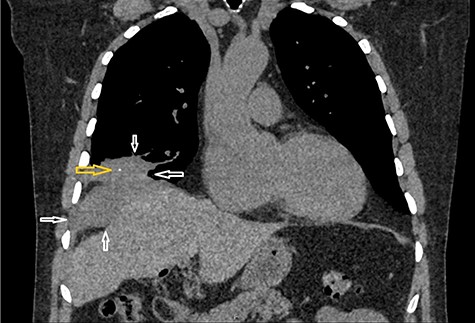

CT scan abdomen demonstrates a retroperitoneal abscess tracking through an intramuscular opening onto skin in the right paraspinal region.

A CT scan abdomen was performed, which demonstrated a large retroperitoneal abscess behind the liver tracking through a small intramuscular opening onto the skin over the upper aspect of the back (Fig. 2).